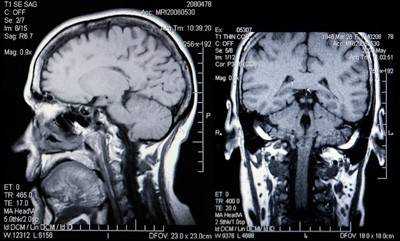

Фото томографии аденомы гипофиза

Опухоль гипофиза на МРТ выглядит как участок округлой формы с четкими границами

Макроаденома гипофиза на снимке МРТ

Выявление микроаденомы гипофиза с помощью МРТ: изображения в разных проекциях

Гигантская аденома гипофиза на МРТ